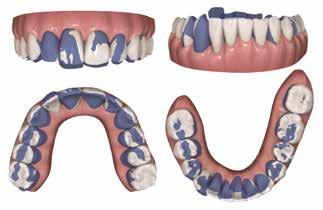

INTRODUKTION OG FORMÅL – Ortodontisk behandling kan være en nødvendighed hos patienter med avanceret parodontitis (stadie 3 og 4), hvis der skal genetableres funktionel okklusion, tilfredsstillende æstetik samt være mulighed for indsættelse af tanderstatninger. Formålet med denne artikel er at præsentere kliniske retningslinjer og en behandlingsmodel for ortodontisk behandling af patienter med velbehandlet parodontitis.

MATERIALE OG METODER – Artiklen bygger på en gennemgang af internationale retningslinjer og kliniske erfaringer, herunder to patienttilfælde, hvor der er foretaget ortodontisk behandling af patienter med stadie 3- og 4-parodontitis. Der beskrives rammer for en systematisk tilgang med fokus på parodontal sundhed, ortodontisk korrektion og livslang vedligeholdelse, hvor hele behandlingen udføres i et tæt interdisciplinært samarbejde.

RESULTATER – Begge patienter opnåede sunde parodontale forhold, funktionel okklusion og forbedret æstetik. Ortodontisk behandling blev iværksat efter opnåelse af parodontal stabilitet og tilpasset det reducerede parodontium med kontrollerede kraftsystemer. Under behandlingen blev parodontiet vedligeholdt, og efter afsluttet ortodontisk behandling blev patienterne fulgt med regelmæssige kontroller af både parodontal sundhed og ortodontisk retention.

KONKLUSION – Ortodontisk behandling af patienter med velbehandlet parodontitis er mulig og kan give gode æstetiske og funktionelle langsigtede resultater med en interdisciplinær tilgang og efterfølgende fokus på vedligeholdelse og retention.

Vi viser her to ortodontiske behandlinger af patienter med velbehandlet stadie 3- og 4-parodontitis, som begge har tandtab og reduceret, men sundt parodontium, dog med begrundet undtagelse af en enkelt tand, som vi kommer tilbage til. Behandlingerne følger følgende princip:

PATIENTTILFÆLDE 1

Patienttilfælde 1 (Fig. 1) er en 37-årig kvinde, henvist efter succesfuld behandling af stadie 3-parodontitis. Der er nu sundt

Før behandling

parodontium, ingen pocher over 4 mm, og både blødnings- og plakindeks er under 10 %. Patienten er motiveret for ortodontisk behandling, da hendes tænder er vandret over tid, delvist som følge af reduceret parodontium.

Der ses anterior trangstilling i begge kæber og overerupterede 1+1 og 2,1-1,2, hvilket resulterer i dybt bid med 2- tæt på ganepåbidning. Der er normale sidetandsrelationer, men der ses 5 mm horisontalt overbid (HOB) og 7 mm vertikalt

overbid (VOB). Papillen mellem 1+1 er betydeligt reduceret pga. fæstetab, og de mesialt kippede 1+1 har resulteret i en ”dark triangle”. Den facioorale funktion er for nuværende i.a. Panoramarøntgen (Fig. 1, I) viser marginalt knogletab i begge kæber og fravær af 8,7+7,8 og 8,7-8.

Objektivt anbefales behandling af det dybe bid, som ubehandlet forventes at forværres yderligere over tid. Patienten har ønske om behandling med æstetisk ortodontisk apparatur, alignere, og det vurderes muligt at behandle malokklusionen med alignere. Dog anbefales det generelt, at alignere undgås eller benyttes med væsentlige modifikationer af alignerens retention ved tandmobilitet, da dette ellers kan medføre jiggling, når aligneren tages af og på mange gange dagligt. På den anden side er der nogen evidens for, at alignerbehandling er associeret med bedre renhold og parodontal sundhed sammenlignet med fast apparatur (16).

Ortodontisk behandling af patienter med parodontitis kan ofte foretages sikkert ved at følge en systematisk tilgang, der omfatter 1) inflammationskontrol, 2) ortodontisk korrektion og 3) livslang vedligeholdelse. Inden behandlingen påbegyndes, skal parodontiet generelt være sundt med pocher på maksimalt 4 mm og et plak- og blødningsindeks under 10 %. Restfæstet skal være tilstrækkeligt til at modstå behandlingen, som udføres med kontrollerede kraftsystemer. Målet er at forbedre æstetik og opnå normal funktion, som kan vedligeholdes på lang sigt samt facilitere restaurerende behandling.

Der planlægges alignerbehandling af begge kæber med intrusion af 1+1 og 2,1-1,2, nivellering af trangstilling UK med interproksimal reduktion (IPR) (Fig. 2 A, B) og senere IPR OK for reduktion af dark triangles mellem incisiverne efter nivellering. Patienten instrueres i at benytte alignere 20-22 timer/ dag med alignerskift hver 7. dag, og patienten ses hver 3.-8. uge under forløbet. Den første alignerserie består af 16 alignere for nivellering OK/UK og IPR i UK (Fig. 2). Efter denne serie planlægges IPR mellem incisiverne i OK for reduktion af dark triangles (Fig. 3) samt yderligere intrusion af OK og UK-fronten i 12 refinement-alignere. Patienten udviser god kooperation og er meget tilfreds med alignerapparaturet, som er mindre synligt end det faste apparatur (Fig. 4).